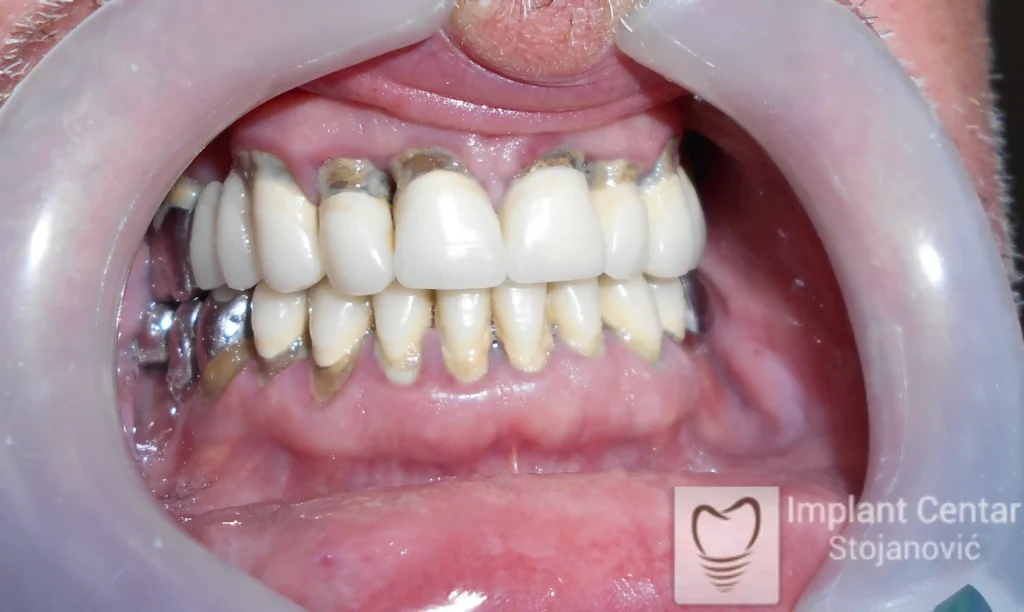

Pacijent je došao sa starim, dotrajalim mostovima koji nisu pružali adekvatno samopouzdanje niti estetski izgled. Nakon detaljnog kliničkog pregleda i analize, izrađen je plan terapije koji je podrazumevao skidanje postojećih mostova i vađenje zuba koji nisu mogli da pruže podršku novom fiksnom protetskom radu.

Ugradnjom optimalnog broja implantata obezbeđena je dugotrajna stabilnost protetskog rada i pravilan raspored sila pri žvakanju. Definitivne cirkonijum-keramičke krunice omogućile su maksimalnu estetiku, funkciju i vraćeno samopouzdanje pacijenta.